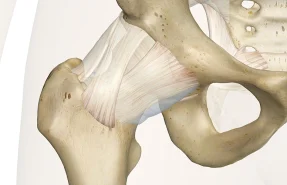

تزریقات داخل مفصلی

روشی کم تهاجمی برای کاهش درد و التهاب مفاصل است که معمولا با داروهای استروئیدی یا هیالورونیک انجام می‌شود. این روش به بهبود حرکت مفصل و کاهش نیاز به جراحی کمک می‌کند.